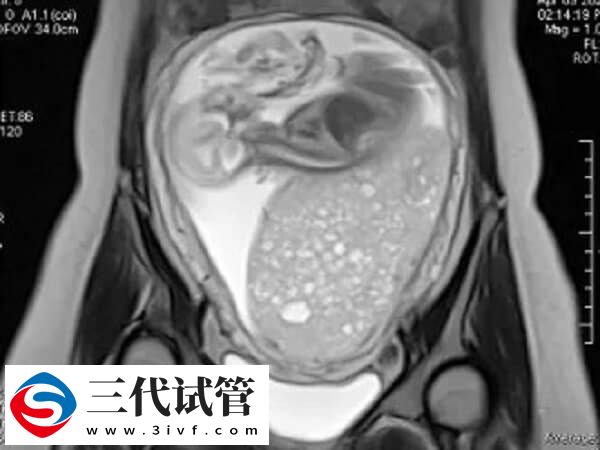

“卵巢”的功能是产生“卵子”。卵子与卵泡中的卵泡同步成熟。发育良好的卵子是试管婴儿成功的保证。然而,这些卵太小,肉眼看不见。为了在试管婴儿中成功获得优质卵子并将其制成胚胎,卵子的发育只能通过观察卵泡间接推断。在卵泡发育过程中,一种更简单直观的评估方法是通过超声进行观察。通过每个周期3-4次的超声监测,我们可以观察是否有正常的卵泡生长、发育,以及何时可以进行取卵手术。

在试管婴儿超排过程中,卵泡监测是为了评估卵巢刺激的效果,并确定取卵的时间。当两个以上的卵泡直径大于18mm时,“夜针”可以在当天注射人绒毛膜促性腺激素(HCG),以促进卵泡的成熟。注射HCG后36小时收集卵。